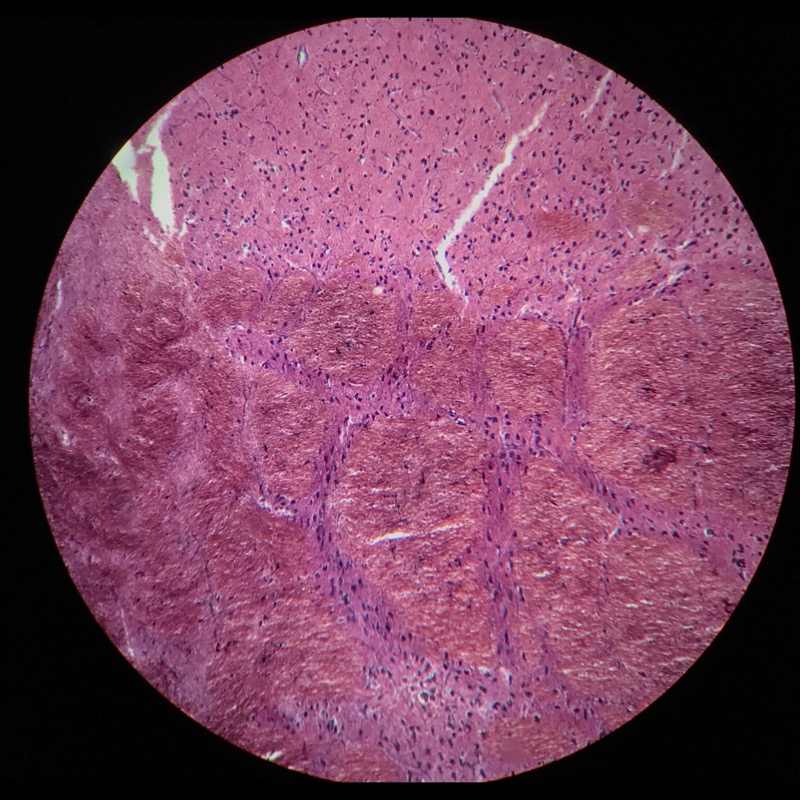

| 1:8:3 | Cerebellum cortex | ![]() ![]() ![]() ![]() |

| 1:8:4 | Cerebellum cortex, Gallocyanin | ![]() ![]() ![]() ![]() |